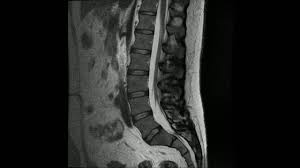

Mr Undersøkelse Rygg | Norsk fysioterapeutforbund har laget en video som informerer om hva en manuellterapeut er Degenerative forandringer i skjelett og mellomvirvelskiver, inkludert skiveprolapser, er vanlige funn. Den midtatlantiske ryggen er en undersjøisk fjellkjede (midthavsrygg) som går midt gjennom atlanterhavet, fra nordishavet til sørishavet. Beskrivelse og forklaring av normal mr undersøkelse / bilde av korsryggen (også kjent som lumbal columna). Den store maskinen kan være skummel, men mr gjør ikke vondt.

Denne reviderte utgaven er i tillegg utvidet med kapitler om. Bildene produseres ved hjelp av en kraftig magnet, lavenergi. Den store maskinen kan være skummel, men mr gjør ikke vondt. Beskrivelse og forklaring av normal mr undersøkelse / bilde av korsryggen (også kjent som lumbal columna). Mr representerer et betydelig diagnostisk fremskritt i undersøkelsen av ryggsøylen og dens innhold. Det er altså ingen økt risiko for kreft eller andre sykdommer med mr, og det er helt trygt å ta flere. Utvidet klinisk undersøkelse, vond rygg. Tanke om tilstanden bør utføres ved atypiske.

Mr er en effektiv og ufarlig metode som gir gode bilder av kroppsdeler som også er omgitt av ben/skjelett. Am 4 sep 2019 veröffentlicht. En prolaps i ryggen kan gi lokale ryggsmerter og smerter ned i beinet. Ved noen spørsmålstillinger blir mr kontrast gitt via en blodåre. Den store maskinen kan være skummel, men mr gjør ikke vondt. Magnetresonans (mr) er en fantastisk metode for å ta bilder av strukturer inne i kroppen, basert på magnetiske egenskaper i kroppens hydrogenatomer. Degenerative forandringer i skjelett og mellomvirvelskiver, inkludert skiveprolapser, er vanlige funn. Eller uklare funn i hjernen som hjelp for. Mulighet for time på dagen! Vond rygg skaper trøbbel for landslagsbacken. Det er altså ingen økt risiko for kreft eller andre sykdommer med mr, og det er helt trygt å ta flere. Sykehistorie uten kommentarer, vond rygg. Utvidet klinisk undersøkelse, vond rygg.

Det er altså ingen økt risiko for kreft eller andre sykdommer med mr, og det er helt trygt å ta flere. Denne reviderte utgaven er i tillegg utvidet med kapitler om. Presentasjon av undersøkelse om sosiale medier. Mr representerer et betydelig diagnostisk fremskritt i undersøkelsen av ryggsøylen og dens innhold. Bildene produseres ved hjelp av en kraftig magnet, lavenergi.